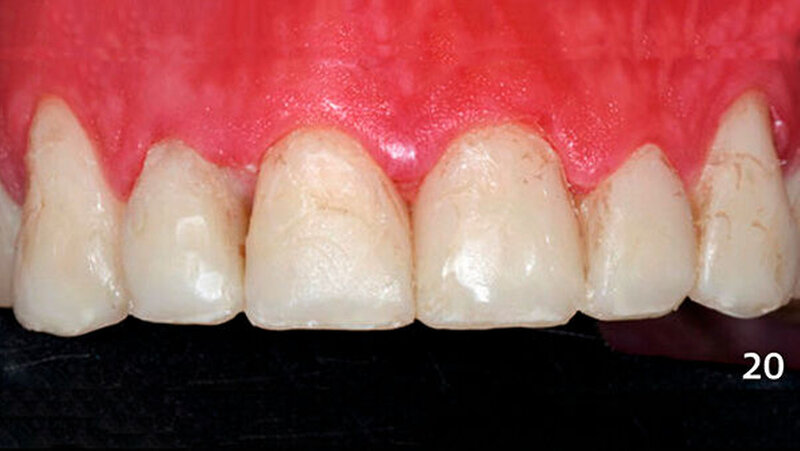

Die Dentinmassen wurden dann von bukkal im inzisalen Anteil mit einer dünnen Schicht Schmelzmasse überschichtet, die im zervikalen Bereich der Zähne mit Bodymasse (Farbe A3B) ergänzt wurde und an diesem Tage aufgrund Zeitmangels nur grob ausgearbeitet wurden. Die Restaurationen stellten sich in der darauffolgenden Sitzung mit oberflächlichen Verfärbungen dar (Abb. 20) und wurden nun vollständig ausgearbeitet und poliert (Abb. 21).